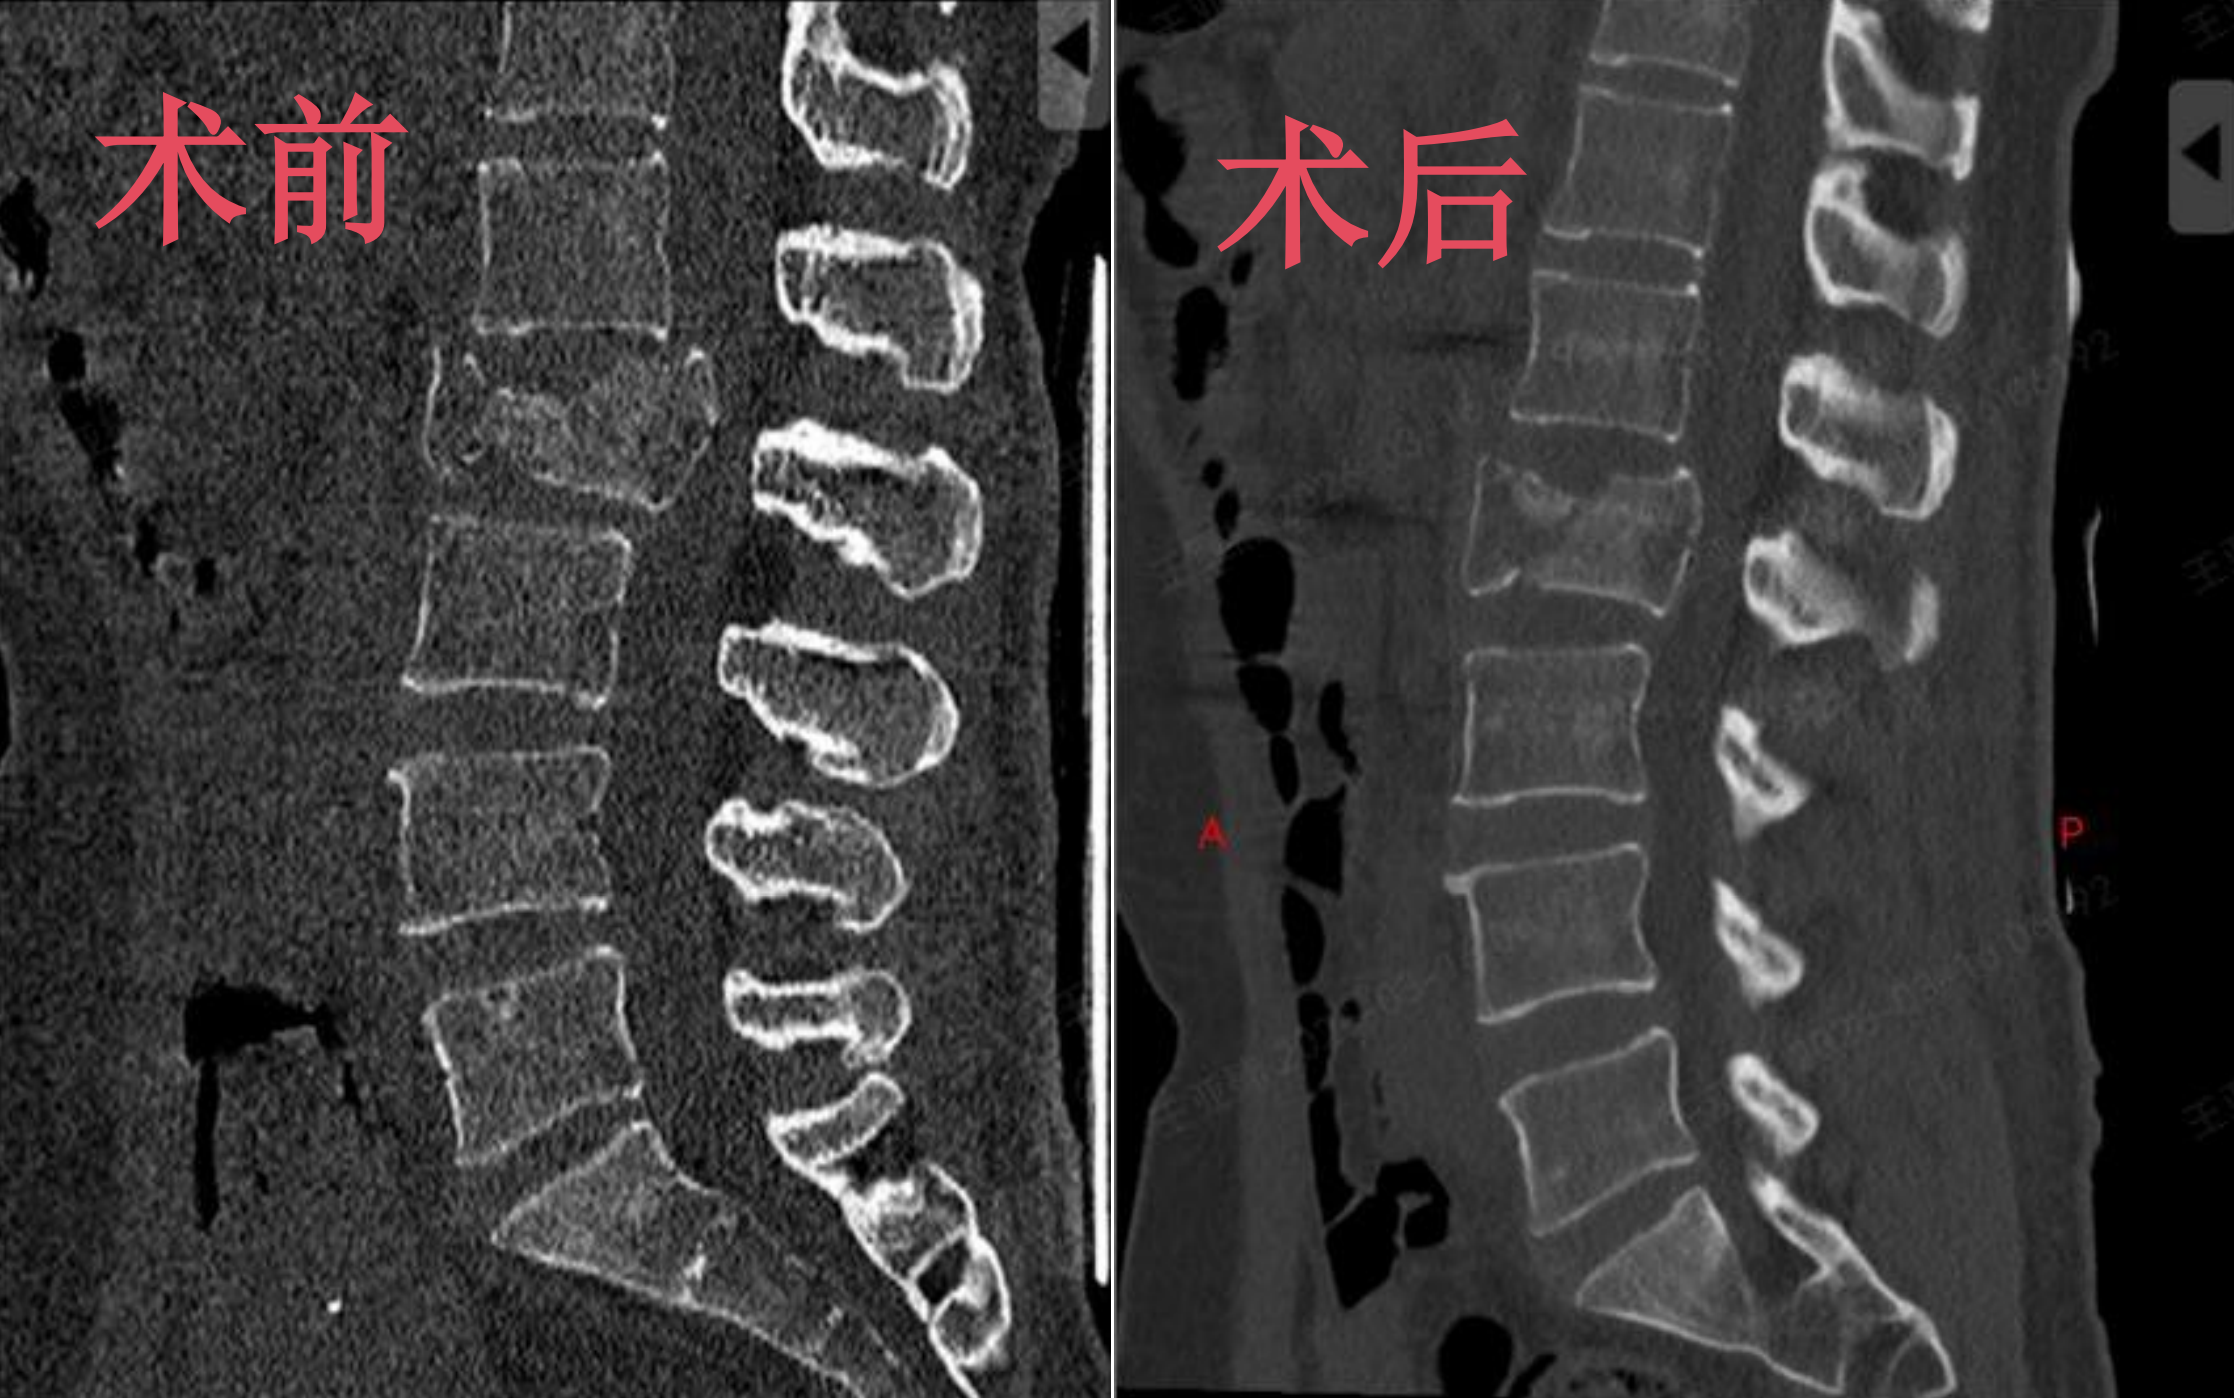

44 岁的王女士(化名)平日里酷爱健身,却因一次健身中的不慎摔倒,突发腰部剧烈疼痛,无法正常活动。家人紧急将其送往我院急诊,经完善的影像学检查后,医生明确诊断其为腰 2 椎体爆裂骨折,骨块已侵犯椎管。万幸的是,王女士暂未出现神经损伤症状,但医生表示,若不及时手术干预,骨折会影响脊柱稳定性,后续还可能遗留神经损伤等后遗症,需尽快开展手术治疗。

考虑到王女士年龄适中,对术后恢复速度、生活质量有着较高的需求,王肖虎主任迅速展开综合评估,结合患者病情与康复期待,为其定制了骨科手术机器人辅助下腰 2 椎体骨折经皮微创椎弓根螺钉内固定术的个性化治疗方案。

相较于传统开放手术,机器人导航辅助置钉的优势十分显著:无需大面积剥离椎旁肌肉,仅在皮肤上做几个微小切口,借助机器人的精准定位系统,即可将螺钉准确植入目标椎体,最大限度减少对周围组织的损伤,从源头降低手术风险,契合了患者的康复需求。

手术中,在王肖虎主任的带领下,手术团队配合默契,骨科手术机器人充分发挥精准导航作用,凭借专业的导航系统实时捕捉患者脊柱的解剖结构,精准引导螺钉植入的角度与深度,全程实现可视化操作,有效规避了神经、血管等重要组织受损的风险,整个手术过程顺利完成。